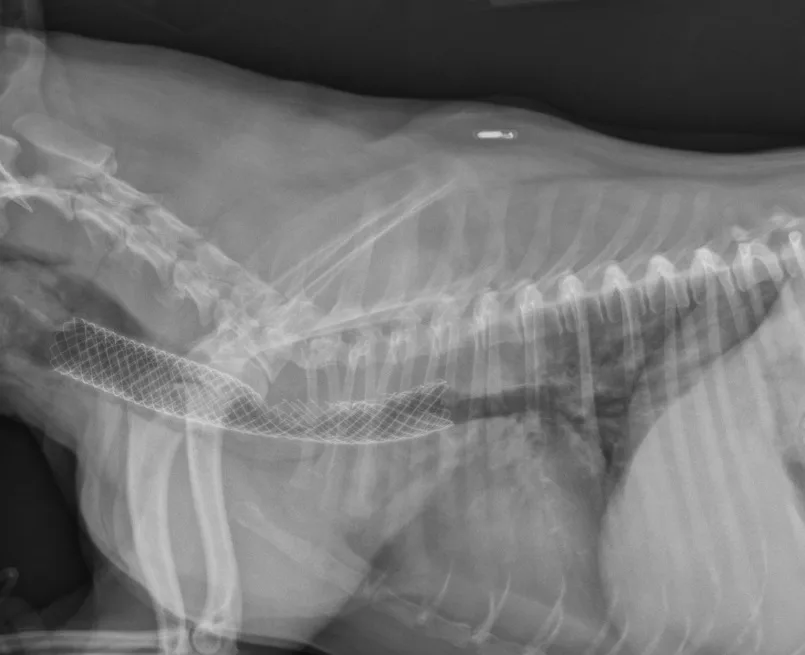

Many surgeons prefer intraluminal stents because they can be noninvasively placed in the cervical or thoracic trachea, reducing risk for complications and shortening anesthetic times. Vet Stent–Trachea is a woven, reconstrainable, self-expanding, nitinol stent3-8 (Figure 3). Nitinol, a nickel–titanium alloy, has thermal shape memory, super elasticity, and elastic hysteresis; the latter minimizes outward force on the interior lumen of the trachea, regardless of stent size.24 The undeployed intraluminal stent is secured within a low-profile delivery system that has radiopaque markers to facilitate positioning. As it is released from the catheter, the stent expands to meet the internal wall of the trachea, foreshortening as it increases in diameter. Because the stent is reconstrainable, it can be pulled back into the delivery system for repositioning after partial release.

Fully deployed stent. Courtesy of Infiniti Medical.

Partially deployed stent. Courtesy of Infiniti Medical.

The flexibility of woven nitinol stents allows them to maintain their cylindric shape along the length of the trachea, despite changes in tracheal direction or diameter. Radial stress applied to the interior lumen of the trachea prevents migration of the stent, as long as an appropriate size is chosen.2,26

Preferred stent size is estimated from survey radiographs taken with the patient under general anesthesia. A probe marked with radiopaque lines at 1-cm increments is placed within the esophagus to permit correction associated with potential magnification. The endotracheal tube is retracted to where the cuff is inflated within both the cricoid and thyroid cartilages, and the trachea is expanded with positive pressure to determine maximal lumen diameter. Length is measured from the caudal surface of the cricoid cartilage to the cranial edge of the carina. Tracheobronchoscopy can be used to recheck the length of the trachea, determine the grade of collapse, and obtain samples for culture and cytology.

Stent selection is based on matching the desired stent diameter and length with measurements in the manufacturer’s foreshortening chart, which provides an estimate of final length based on the predicted diameter of expansion. The stent should span from just caudal to the cricoid cartilage to just cranial to the tracheal bifurcation. Final stent width should exceed the maximal diameter of the trachea by 10% to 20% to prevent stent migration.